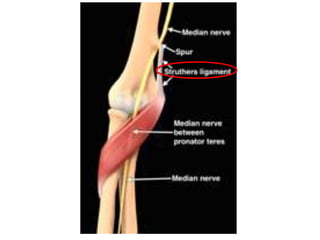

Medial Nerve

1. Supracondylar process

2. Ligament of Struthers

3. Lacertus Fibrosus

4. Heads of PT

5. FDS aponeurotic arch

Pronator Syndrome

• Reduced sensation with

repetetive rotation of forearm

• Includes palmar cutaneous

branch

• Fatigue of forearm muscles

• Tinels positive in proximal

forearm NOT at wrist

• Resisted flexion of long and ring

fingers may cause forearm pain

• Resisted elbow flexion + forearm

• Nb-coexisting golfers elbwo